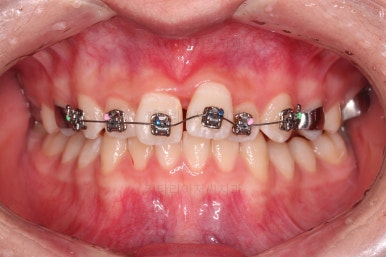

3. 치료경과

악궁확장부터 시행합니다.

확장이 잘 되어 앞니 사이에 틈새도 잘 벌어진 것이 확인되고요.

적절한 시기에 시차를 두고 순차적으로 브라켓을 부착합니다.

이번 환자분이 선택한 브라켓은 자가결찰 메탈의 한 종류인 엠파워 메탈 장치였습니다.

흔히들 아시는 클리피씨와 같은 자가결찰 타입이며, 성분만 금속성이라 눈에 좀 더 잘 띈다는 특징이 있지만 부피도 좀 더 작고 튼튼하며 좀 더 저렴한 장점이 있습니다.

장치 부착 직후의 눈에 보이는 모습과 옆라인의 변화 확인해 주시고요.

이번 환자분은 장치를 부착했다고 해서 옆라인이 거의 차이가 나지 않는 케이스였습니다.

적절한 시기에 아랫니도 장치를 구성하고요.

과개교합 및 앵글씨 2급 부정교합 개선을 도와주는 장치도 보조적으로 활용해 주었습니다.

가지런한 느낌은 좋아졌고, 과개교합도 깔끔하게 개선이 되었습니다.

이제부터는 부정교합을 개선하면서 위아래 어금니 맞물림을 개선해 나갑니다.